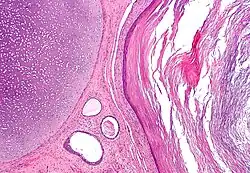

Teratom je nádor složený z různých tkání, které v daném místě normálně nebývají a které vznikly z embryonální tkáně. Často bývá v pohlavních žlázách. Má různý stupeň zralosti a podle toho i stupeň zhoubnosti teratokarcinom. Teratomy mají obvykle podobu vaku různé velikosti, které v sobě obsahují známé tkáně či orgány např. zuby, vlasy, kost, vzácně i oko.[1]